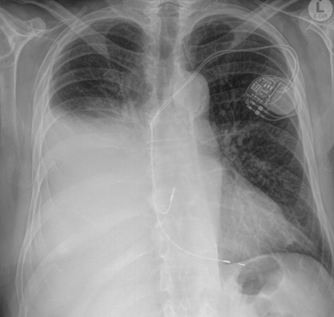

tachyarrhythmia. He had no other comorbidities. An initial baseline chest X-Ray

(CXR) performed on 26 May 2024 revealed a right pleural effusion (Figure 1).

Figure 1. CXR performed on 26 May 2024.